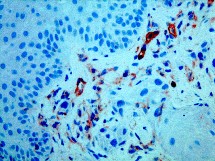

CD34

Para obtener este resultado revolucionario, los investigadores, especializados en hematología, seleccionaron y situaron las células madre de la sangre presentes en la médula ósea y bautizadas como «CD 34 », que son células que están perfectamente identificadas y que ya se usan para hacer transplantes de médula. Estas células se encuentran también en la sangre de los cordones umbilicales.

Los hematólogos han conseguido inducir la proliferación de estas células en una cantidad importante, así como « forzarlas » a diferenciarse hacia una forma particular de células sanguíneas: los glóbulos rojos, a partir de una célula, la « CD 34 ». De ella se pueden obtener entre cien mil y dos millones de glóbulos rojos.

Ha sido la reproducción en laboratorio de un micro-entorno similar al que las células tienen en la médula ósea, el que ha permitido que las llamadas células “CD 34” produzcan glóbulos rojos maduros, esto es, sin núcleo.